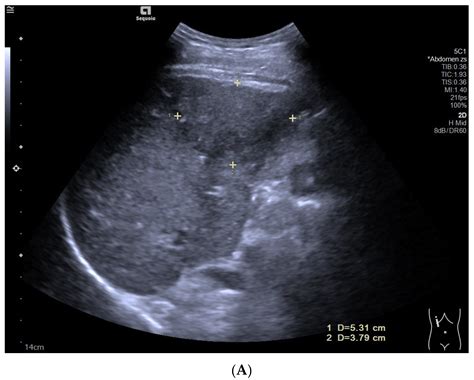

When clinicians review liver ultrasound images, they look for changes in size, shape, and internal patterns. The consistency of the liver’s surface and the presence of any masses are critical markers for diagnosing conditions ranging from simple cysts to more complex oncological issues.

Hepatic Cysts Well-defined, thin-walled, and anechoic (black) circular structures.

Cirrhosis Coarse, heterogeneous texture with an irregular, nodular liver surface.

If an ultrasound scan reveals an abnormality, it does not always indicate a grave diagnosis. Many findings, such as simple hepatic cysts, are benign and require no intervention. However, liver ultrasound images that show unusual masses or signs of significant scarring (cirrhosis) may prompt further diagnostic investigations.